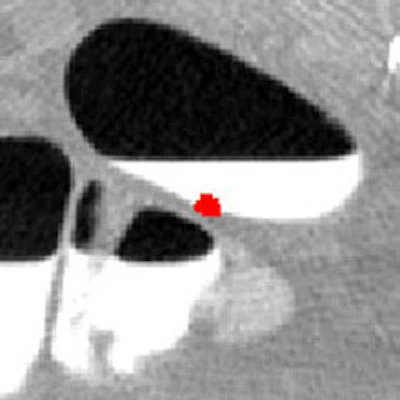

| Above and below: Images from a second clinical case demonstrate adaptive correction with CAD. Top, lesion (arrow) covered by tagged fluid, seen with lung display window. Below, soft-tissue display window shows distortion of the polyp. Third from top, CT-value correction reduces polyp distortion. Bottom, CAD detection overlaid on lung display window. |

![]() |